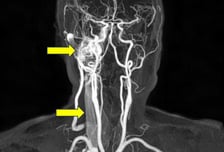

귀에서 심장 박동 소리처럼 반복적인 두근거림이 들린다면 이를 '박동성 이명'이라고 한다. 이 소리가 장기간 들린다면 단순한 이비인후과적 문제가 아니라 심각한 혈관성 질환이나 전신성 질환의 신호일 수 있다. 과연 박동성 이명은 어떤 병의 지표일 수 있을까? 서울특별시보라매병원 이비인후과 김영호 교수의 도움말로, 박동성 이명에 대해 알아본다. ━혈류 변화나 구조 이상으로 맥박성 소리 들려━박동성 이명은 귀에서 자기의 심장 박동과 같은 리듬의 소리가 반복적으로 들리는 상태다. "삐-", "윙-"등 일반적인 이명 소리와 달리 "두근두근", "둥둥둥" 같은 맥박성 소리가 특징적이다. 박동성 이명은 일반적인 이명과 달리 실제 혈류 변화나 신체 구조적 문제 같은 객관적 요인이 있을 가능성이 커, 정확한 진단과 원인 규명이 필수다. 박동성 이명은 일반적인 이명보다 발생 빈도는 낮지만, 전체 이명 환자 가운데 많으면 10%까지도 차지할 정도여서 무시할 수 없는 질환이다. 하지만 일반적인 이명과 달리